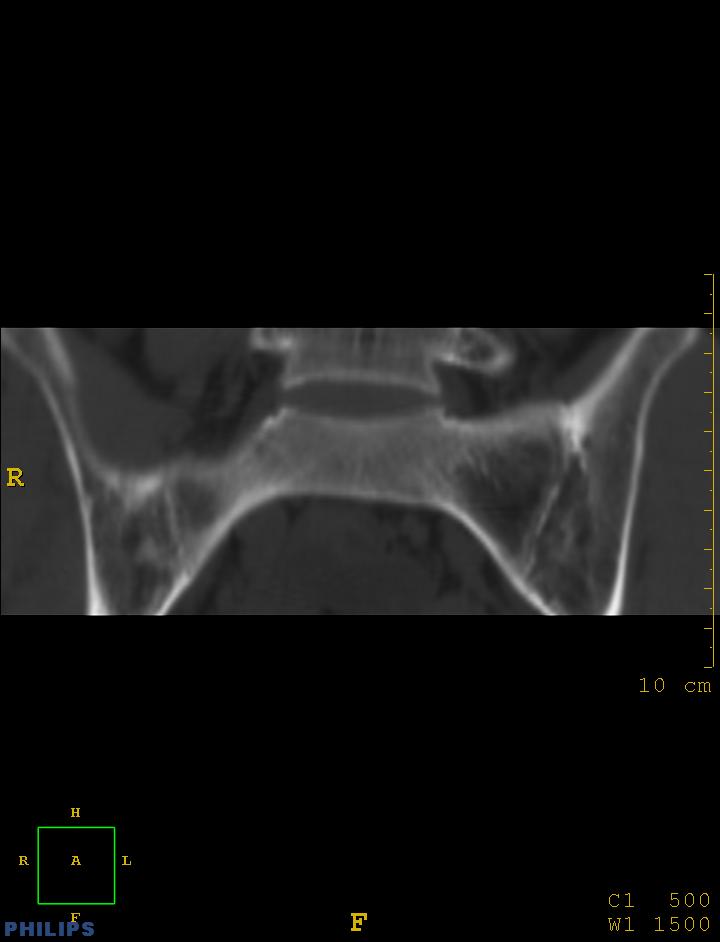

标题: CT14032:M34Y,双侧骶髂关节 [打印本页]

标题: CT14032:M34Y,双侧骶髂关节

m,34岁,腰痛三年,腰椎活动度明显减低,x片示腰椎竹节样改变

双侧骶髂关节骨性融合,软骨下囊性变,结合脊柱竹节样改变,典型的强直性脊柱炎。